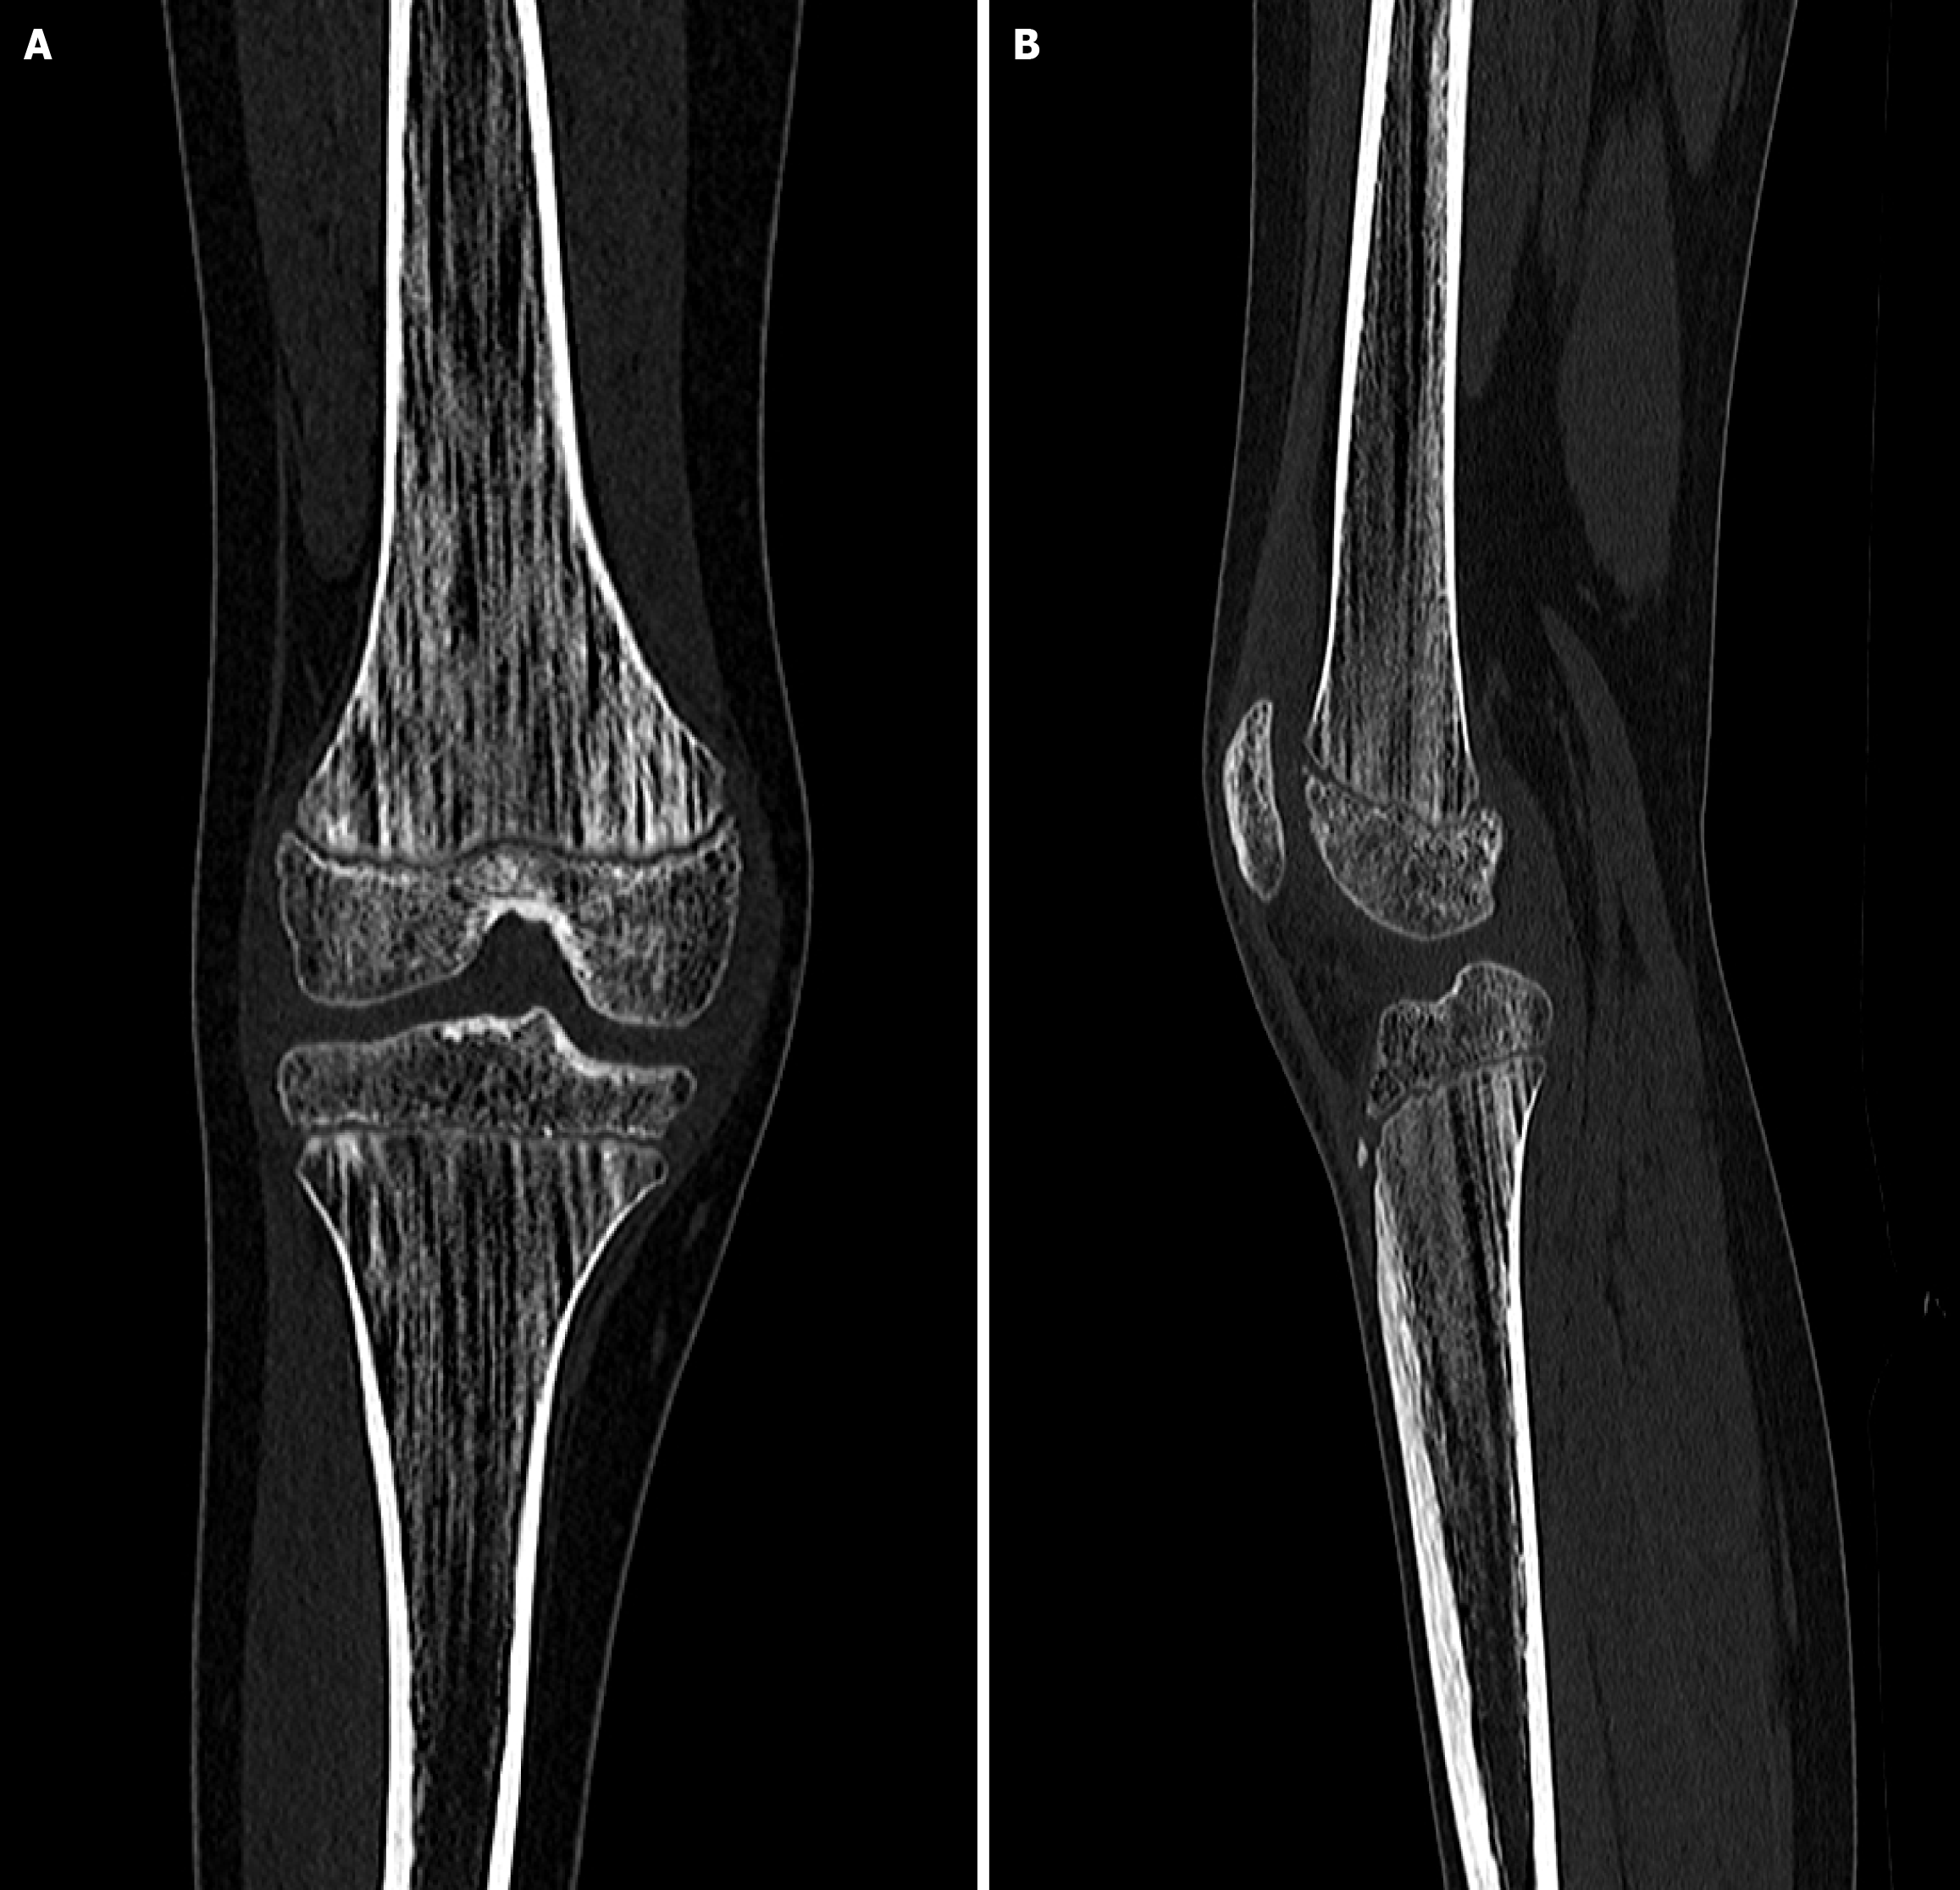

Figure 2

Vertical striations in the metaphyseal regions of the femoral and tibial bones on radiographs.

Figure 3 Vertical striations in the metaphyseal regions of the femoral and tibial bones on computed tomography scans.

A: Posterior view; B: Lateral view.